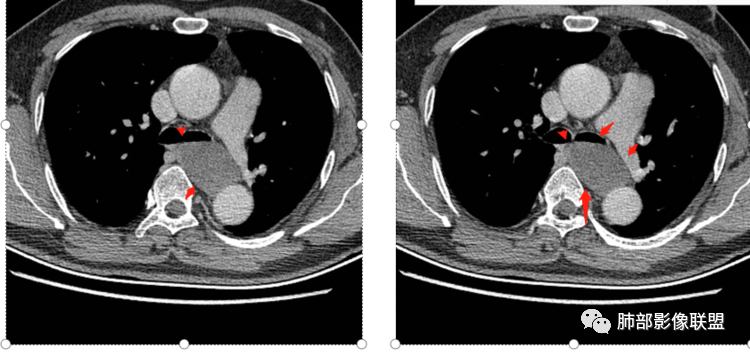

气管、左主支气管后方,食道左侧囊性占位,壁薄且均匀、光滑。气管及左主支气管受压凹陷、变形。

食道也受压变形、移位。

(1)圆形或椭圆形、边缘光滑的病灶,囊壁薄,囊壁可见钙化;由于病变的支气管起源性,囊壁可见属于气管壁的软骨成份.

(2)囊液密度均匀,根据性质的不同而呈不同密度,可为近似水样密度,也可为较高密度,因为囊壁分泌粘液,所以囊内密度一般高于其他纵隔囊肿,CT值多大于20HU甚至超过60HU;

(3)若囊肿内密度较高时与实性肿块鉴别较为困难,增强扫描囊液无强化为鉴别要点;但是囊壁因为含有平滑肌成份,所以可能环形强化;如果病灶合并感染,病灶壁也会明显强化。

(5)张力不高时可以形态柔顺,成份复杂时可以密度较高,但内部不会强化。